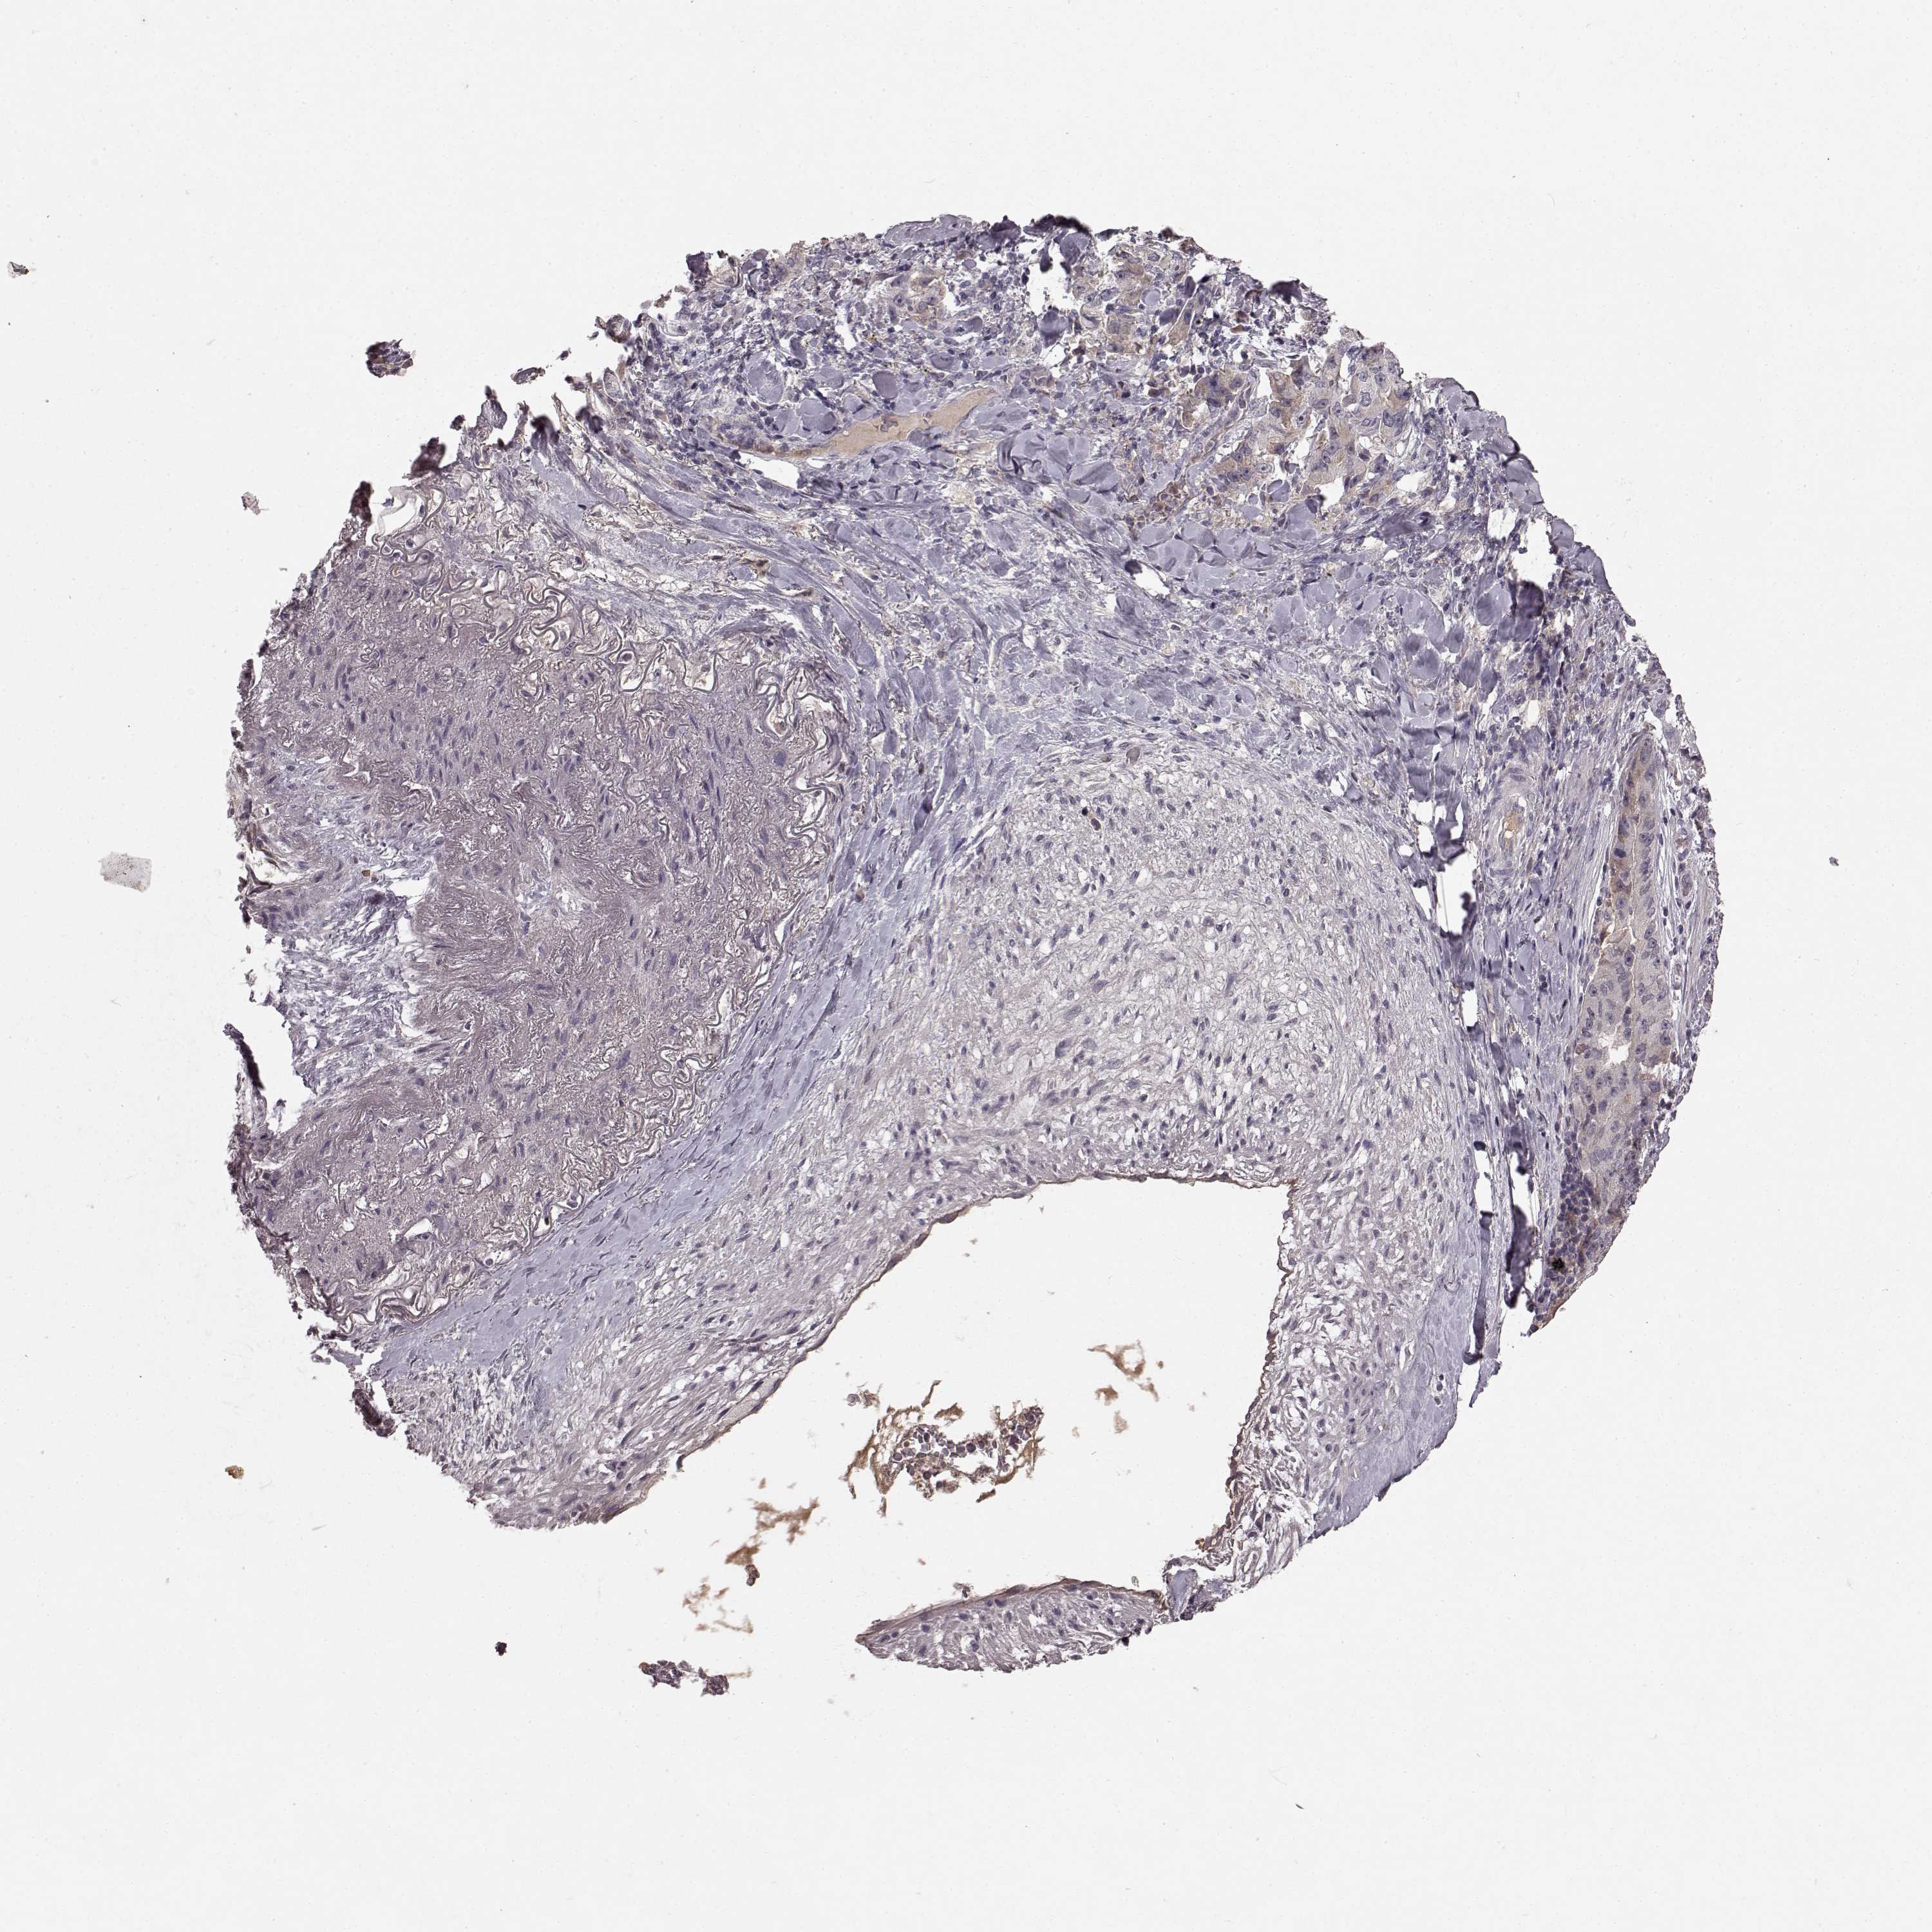

LUNG SQUAMOUS CELL CARCINOMA (TCGA) - Interactive survival scatter ploti

The Survival Scatter plot shows the clinical status (i.e. dead or alive) for all individuals in the patient cohort, based on the same data that underlies the corresponding Kaplan-Meier plots. Patients that are alive at last time for follow-up are shown in blue and patients who have died during the study are shown in red.

The x-axis shows the expression levels (FPKM) of the investigated gene in the tumor tissue at the time of diagnosis. The y-axis shows the follow-up time after diagnosis (years). Both axes are complimented with kernel density curves demonstrating the data density over the axes. The top density plot shows the expression levels (FPKM) distribution among dead (red) and alive patients (blue). The right density plot shows the data density of the survived years of dead patients with high and low expression levels respectively, stratified using the cutoff indicated by the vertical dashed line through the Survival Scatter plot. This cutoff is automatically defined based on the FPKM cutoff that minimizes the p-score. The cutoff can be changed by dragging the vertical line or by entering a cutoff value in the square labeled "Current cut-off".

Under the Survival Scatter plot the p-score landscape (black curve; left axis) is shown together with dead median separation (red curve; right axis). Dead median separation is the difference in median mRNA expression between patients who have died with high and low expression, respectively. It is calculated as follows: median FPKM expression of dead patients with high expression - median FPKM expression of dead patients with low expression. This is intended to aid the user in visually exploring custom cutoffs and the associated p-scores and dead median separation.

Individual patient data is displayed and can be filtered by clicking on one or more of the category buttons on the top of the page. Categories describing expression level and patient information include: high, low, alive, dead, female, male and tumor stages. The scale of the x-axis can be toggled between linear and log-scale by clicking on the "x log" button. Mouse-over function shows TCGA ID, patient information and mRNA expression (FPKM) for each patient.

& Survival analysisi

Kaplan-Meier plots summarize results from analysis of correlation between mRNA expression level and patient survival. Patients were divided based on level of expression into one of the two groups "low" (under cut off) or "high" (over cut off). X-axis shows time for survival (years) and y-axis shows the probability of survival, where 1.0 corresponds to 100 percent.

SLC22A18 is not prognostic in Lung Squamous Cell Carcinoma (TCGA)

: 3.82